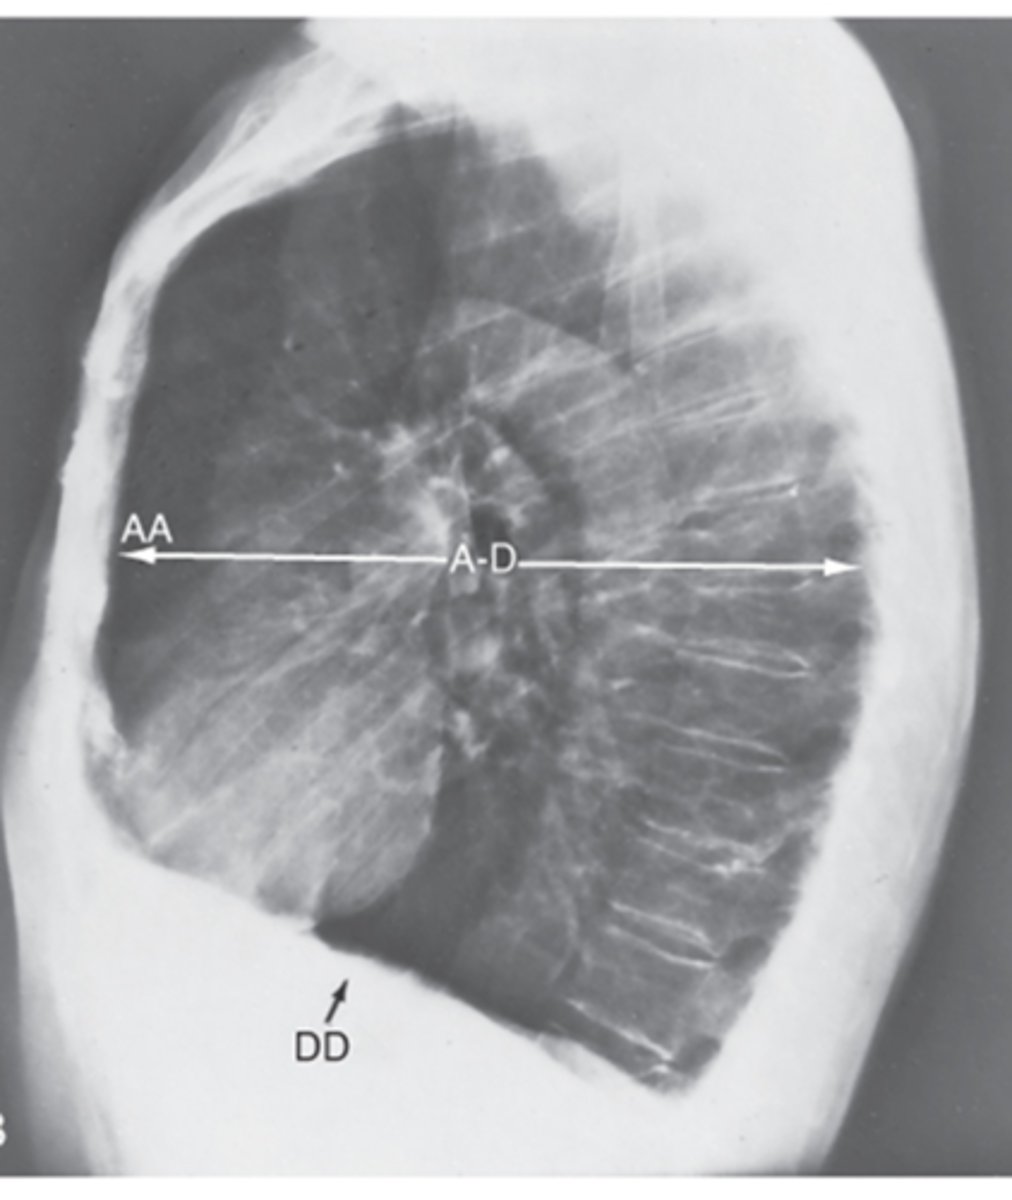

Which view is this?